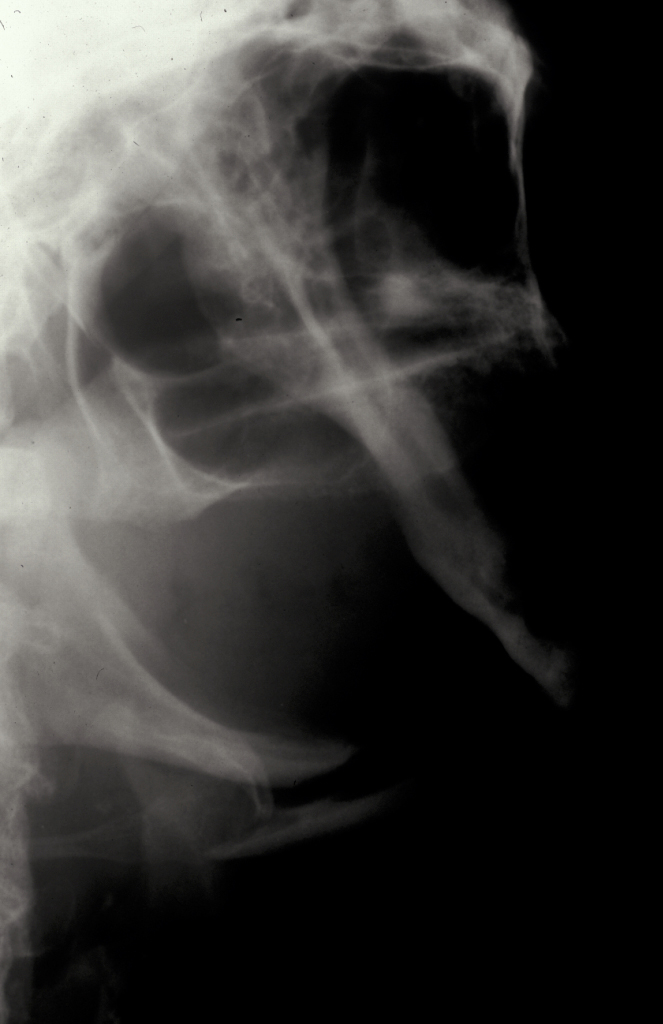

Condylar fractures: these are the most common mandibular fractures. They are treated conservatively in children up to 12 years with soft diet, analgesia and function. Young adults (12-18) are also treated conservatively in the majority of cases. Adults (>18) are treated with 7-10 days of heavy elastic IMF (fixation) and the occlusion reassessed. If malocclusion persists then ORIF of the condyle is undertaken. Overlap of fragments greater than 5 mm and angulation greater than 37°are postulated to warrant ORIF. Logically the function rather than the radiographic appearance should predicate the decision to undertake ORIF (see Figure 9 and Figure 10 for illustration).